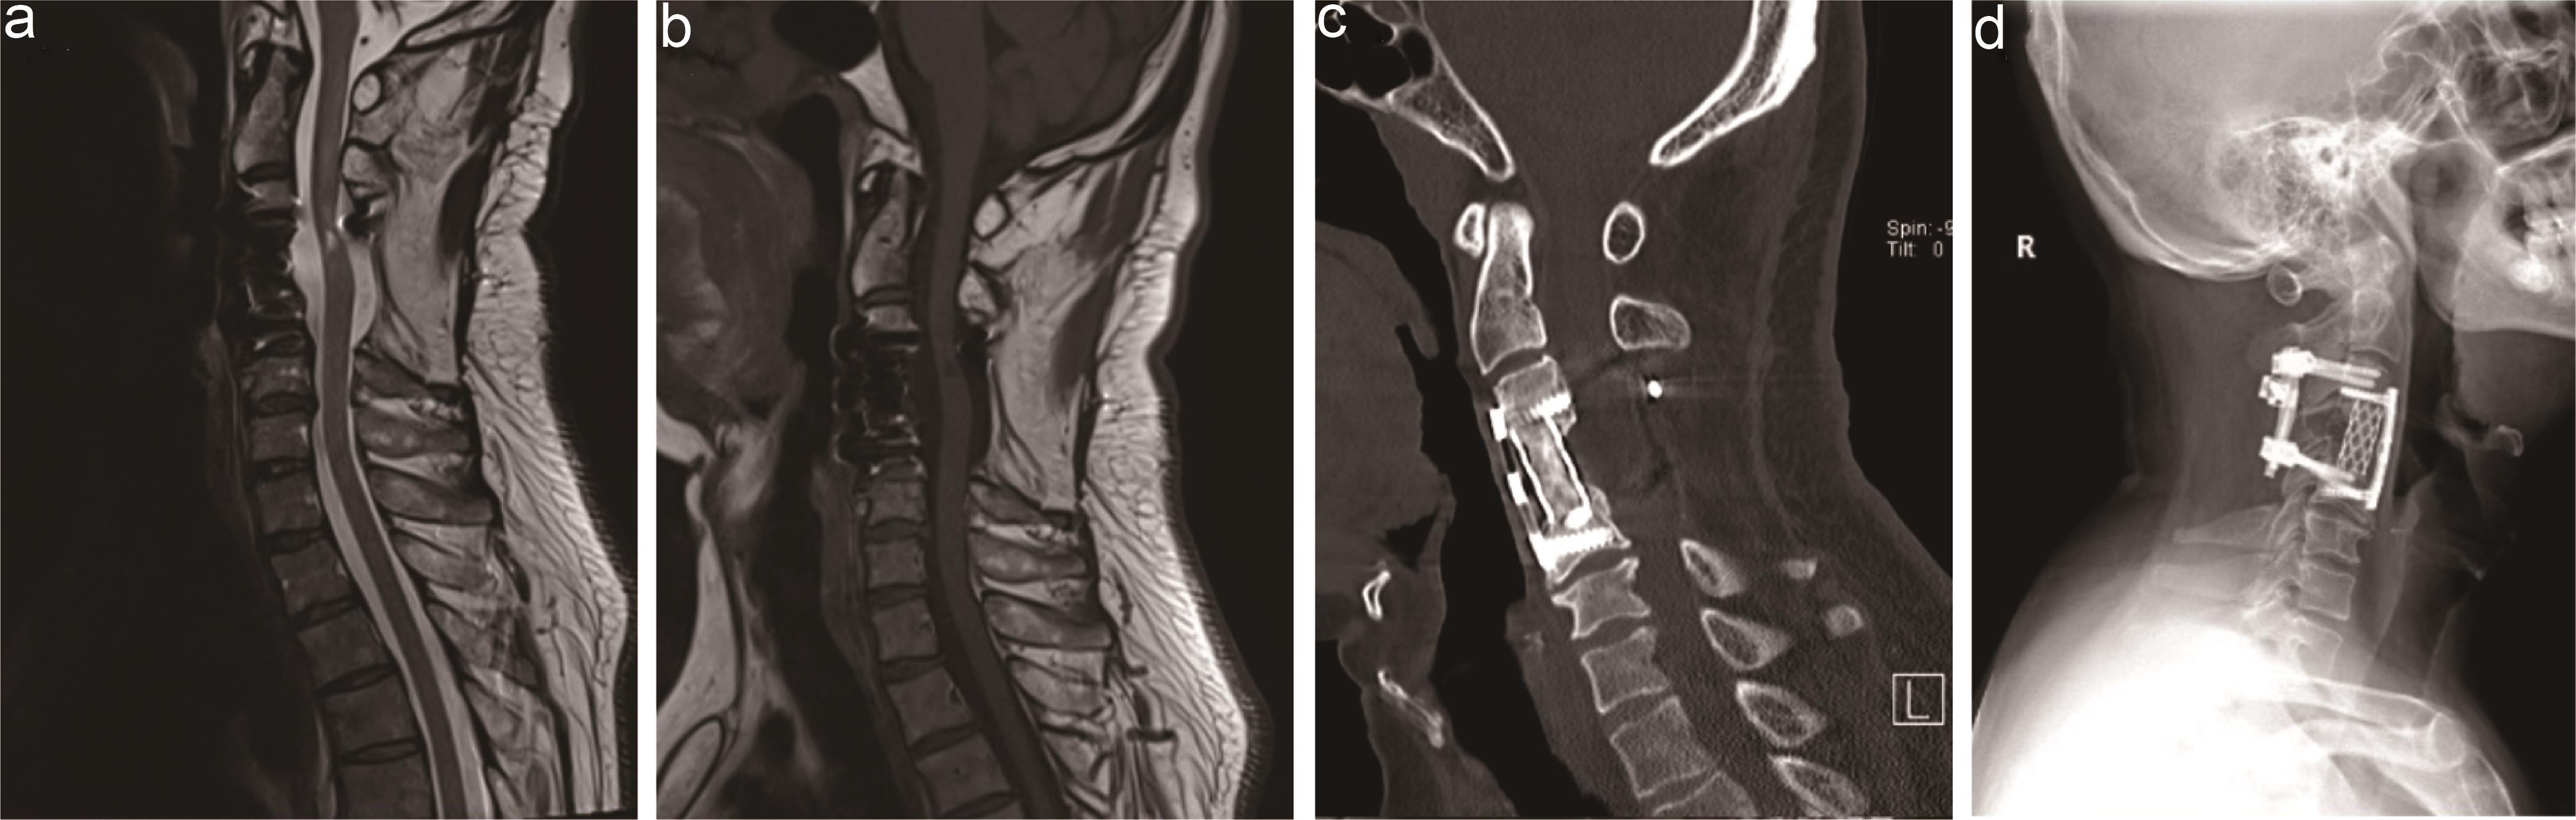

MRI (Fig. 1) of the cervical spine revealed an extradural tumor localized at the C3 to C5 levels, compressing the spinal cord to the left side and invading the C4 vertebral body and its attachments. The tumor penetrated the anterior edge of the C4 vertebral body. Additionally, T2-weighted images revealed the lesion to be hyperintense compared with the spinal cord. After intravenous gadolinium administration, the tumor demonstrated significant enhancement. Computed tomography (CT, Fig. 1) further delineated the VBC of C4 and soft tissue density in the cancellous substance of C4. A comparison of CT (Fig. 1h) and MRI (Fig. 1d and e) images performed at the external hospital in 2017 showed no significant progression in the size of the lesion.

Fig. 1  Preoperative cervical MRI and CT.

Preoperative sagittal (a) and coronal (b) enhanced T1-weighted MRI showed a giant invasive spinal tumor at the C3-5 level. Axial enhanced T1-weighted MRI (c) revealed the tumor with spinal cord compression extended bilaterally across the C3-4 extraforaminal region, surrounded the spinal cord in a “U”-like shape, and invaded the C4 vertebral body (c, arrow 1) and pedicles (c, arrow 2). Compared to the sagittal and axial T2-weighted MRI (d, e) performed in the outside hospital a year ago, the tumor was not enlarged. Preoperative sagittal CT (f) showed C4 vertebral body collapse and soft tissue density in the cancellous substance of C4. Axial CT (g) revealed the tumor eroded bilateral pedicles (g, arrow 3 and 4). Compared to the sagittal CT (h) performed in the outside hospital, it was determined that the C4 vertebral body collapse occurred a year ago. CT, computed tomography; MRI, magnetic resonance image.